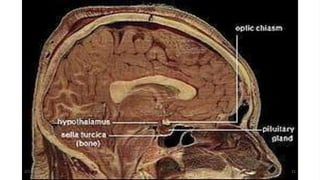

•The hypothalamus is located anterior and

Inferior to the thalamus. The

•It includes the optic chiasm (the point at which

the two optic tracts cross) and the mamillary

2/13/2023 16

emotional response

infundibulum of the hypothalamus connects it

to the posterior pituitary gland.